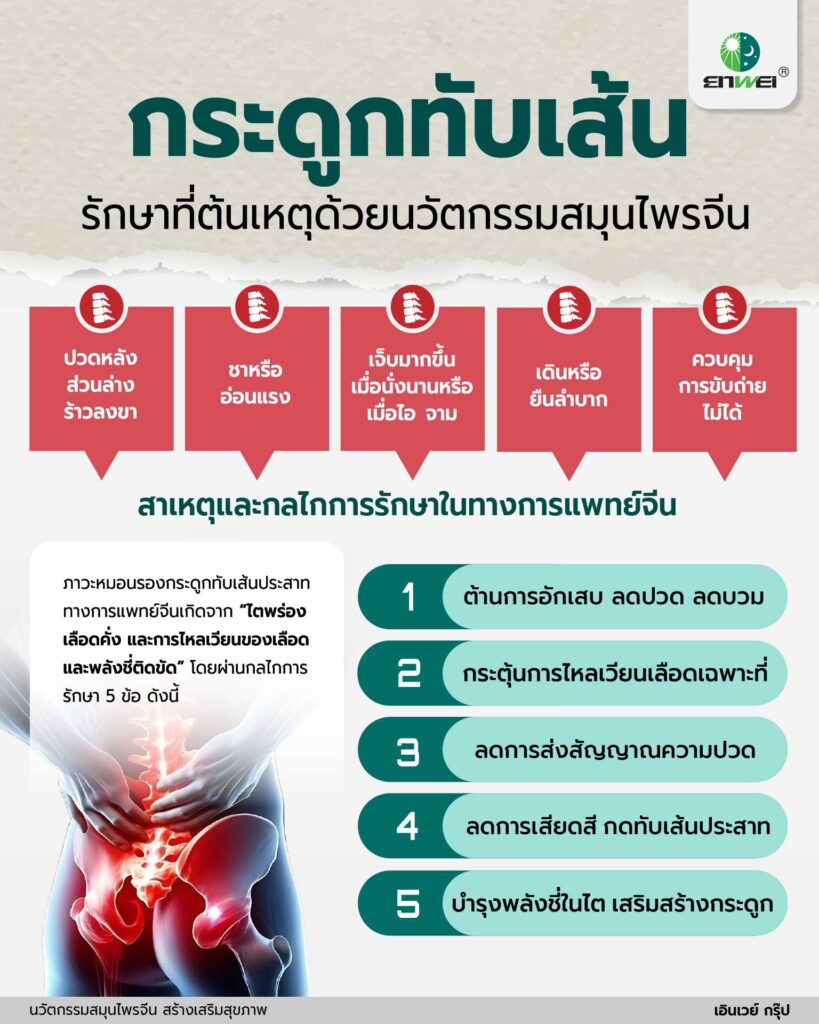

สาเหตุและกลไกของ “หมอนรองกระดูกทับเส้นประสาท”

หมอนรองกระดูกทับเส้นประสาท (Lumbar Disc Herniation) เกิดจากหมอนรองกระดูกสันหลังส่วนล่างเสื่อมหรือเคลื่อนออกมาทับเส้นประสาท ทำให้เกิดอาการ ปวดหลังร้าวลงขา และ ชาที่ขา เป็นปัญหาที่พบได้บ่อยในวัยทำงาน

อาการกระดูกทับเส้น สัญญาณที่ไม่ควรมองข้าม

- ปวดหลังส่วนล่างร้าวลงขา

- ชาหรืออ่อนแรง

- เจ็บมากขึ้นเมื่อนั่งนานหรือเมื่อไอ/จาม

- เดินหรือยืนลำบาก

- บางรายอาจควบคุมการขับถ่ายไม่ได้

หากปล่อยไว้นาน เส้นประสาทอาจเสียหายถาวร ส่งผลให้การเคลื่อนไหวและคุณภาพชีวิตลดลงอย่างชัดเจน

ยาสมุนไพรจีน ฟื้นฟูกระดูกทับเส้นที่ต้นเหตุ

ในทางการแพทย์จีน ภาวะหมอนรองกระดูกทับเส้นประสาทเกิดจาก “ไตพร่อง เลือดคั่ง และการไหลเวียนของเลือดและพลังชี่ติดขัด” ตำรับยานี้จึงออกแบบเพื่อรักษาที่ต้นเหตุ ฟื้นฟูเส้นประสาทและลดการอักเสบ ประกอบด้วยสมุนไพรหลายชนิด เช่น Sanqi, Yanhusuo, Gouji, Duhuo, Niuxi, Chuanxiong ฯลฯ ผ่านการสกัดที่ทันสมัย ควบคุมปริมาณสารออกฤทธิ์ได้อย่างคงที่และแม่นยำ ซึ่งมีกลไกการออกฤทธิ์สำคัญ ดังนี้

- ต้านการอักเสบ ลดปวดและลดอาการบวม

- เพิ่มคอลลาเจนชนิด II ช่วยให้หมอนรองกระดูกยืดหยุ่น ลดการเสียดสีและกดทับเส้นประสาท

- กระตุ้นการไหลเวียนเลือดเฉพาะที่ เพิ่มออกซิเจนให้เนื้อเยื่อ และเร่งการซ่อมแซม

- ลดการส่งสัญญาณปวดในระบบประสาท ช่วยให้ผู้ป่วยรู้สึกปวดน้อยลง

- บำรุงพลังชี่ในไต เสริมสร้างกระดูก ช่วยให้แนวกระดูกสันหลังแข็งแรง ลดโอกาสกลับมาเป็นซ้ำ